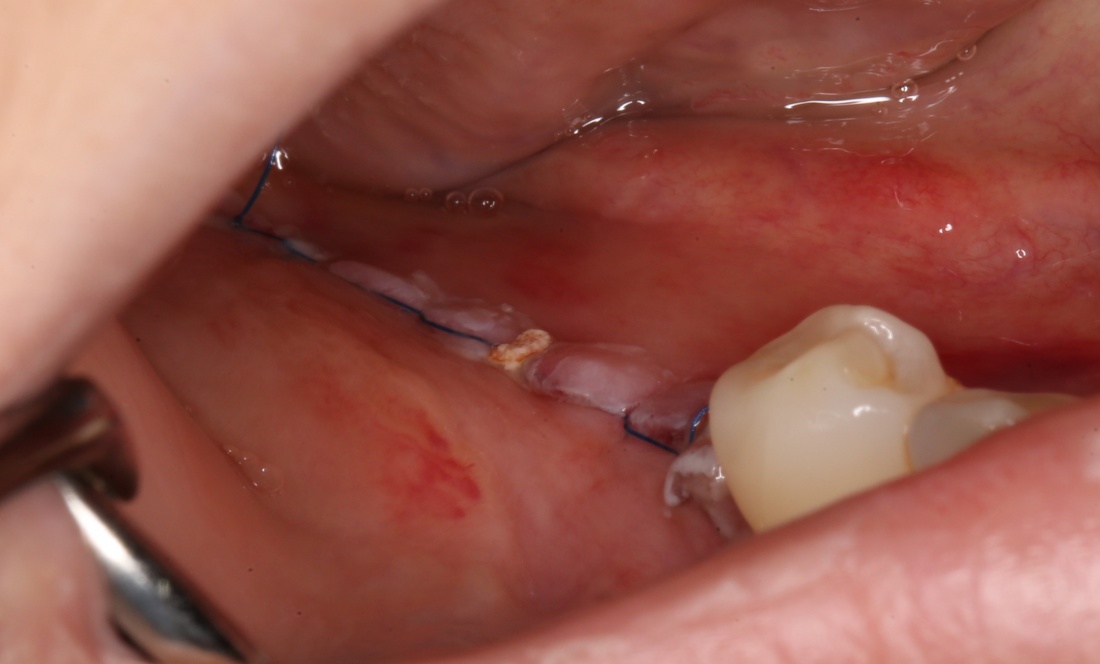

Откроем область операции и посмотрим, что там:

Вроде как, всё неплохо. Наверное, можно поставить имплантаты?

ну, или как-то так:

При этом, я хотел бы обратить ваше внимание на один важный момент. То, с чем вы сейчас работаете — не кость, в привычном нам гистолого-физиологическом понимании. Это костная мозоль вперемежку с графтом. Её свойства довольно сильно отличаются от того, что мы привыкли называть костной тканью. Поэтому при установке имплантатов соблюдайте максимальную осторожность и щадящий режим. Никаких диких торков, усилий, больших переходов между размерами фрез допускать нельзя. Будьте аккуратны.

Иначе, кривокосячной имплантацией вы можете испортить даже мастерски проведенную остеопластическую операцию.